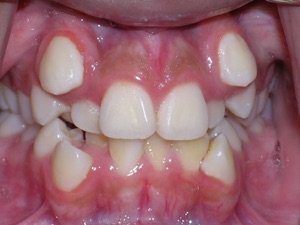

Here’s an example from a young boy who had very significant crowding. One can see that the canines on top and bottom are blocked out. There was also an overbite. The combination made the case challenging. Watch.